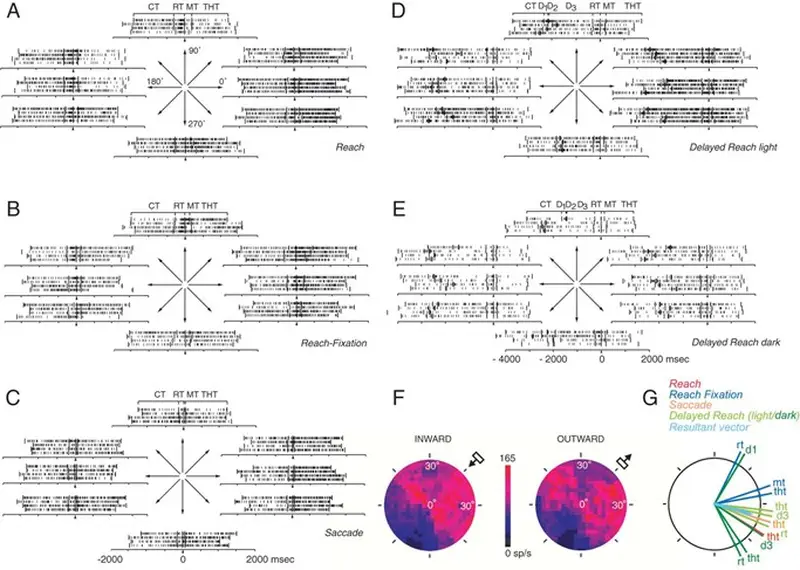

Codifica Precoce del Movimento di Raggiungimento nella Corteccia Parieto-Occipitale

Lo studio analizza l’attività neuronale nella corteccia parieto-occipitale, mostrando come segnali visivi, oculari e motori vengano integrati precocemente per codificare e controllare i movimenti di raggiungimento verso un bersaglio nello spazio.